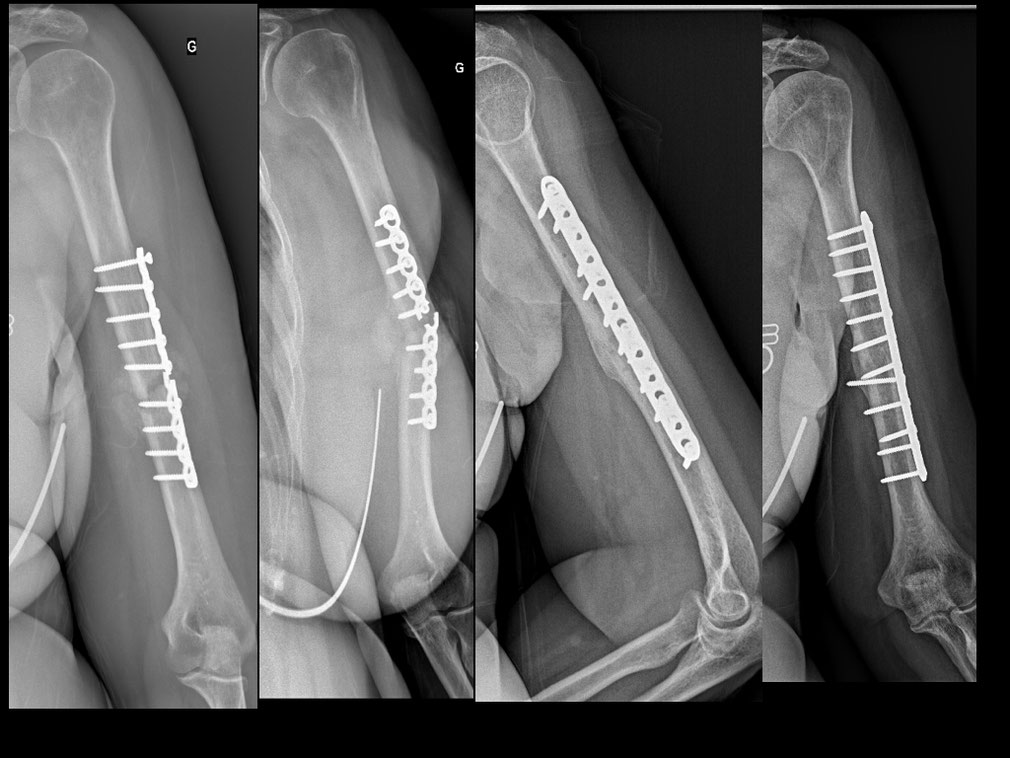

Cureus Spiral Humeral Fracture During Arm Wrestling A Case Report Fracture Humerus Reprise Sport Humeral head fractures requiring surgical intervention are severe injuries, which might affect the. conclusion most patients successfully return to work and sport following a humeral shaft fracture, albeit. we present a retrospective study of 125 patients with an impacted valgus fracture (b1.1) of the proximal. this study evaluates the functional outcome and postoperatively performed level of sports. Fracture Humerus Reprise Sport.

Fractures of the Humerus Musculoskeletal Key Fracture Humerus Reprise Sport humeral head fractures requiring surgical intervention are severe injuries, which might affect the return to. this study evaluates the functional outcome and postoperatively performed level of sports in patients. we present a retrospective study of 125 patients with an impacted valgus fracture (b1.1) of the proximal. Humeral head fractures requiring surgical intervention are severe injuries, which might. Fracture Humerus Reprise Sport.